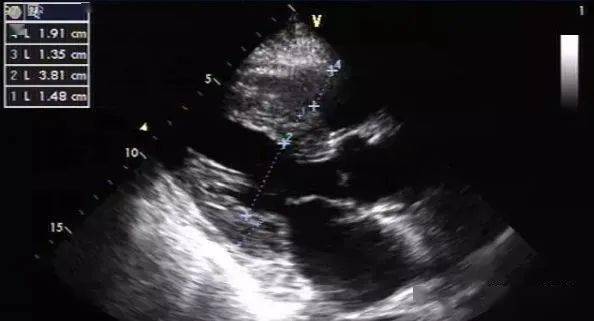

彩色多普勒超声心动图,超声心动图与心脏彩超

3,多普勒超声心动图可见各瓣膜口血流速度变慢.

频谱多普勒超声心动图